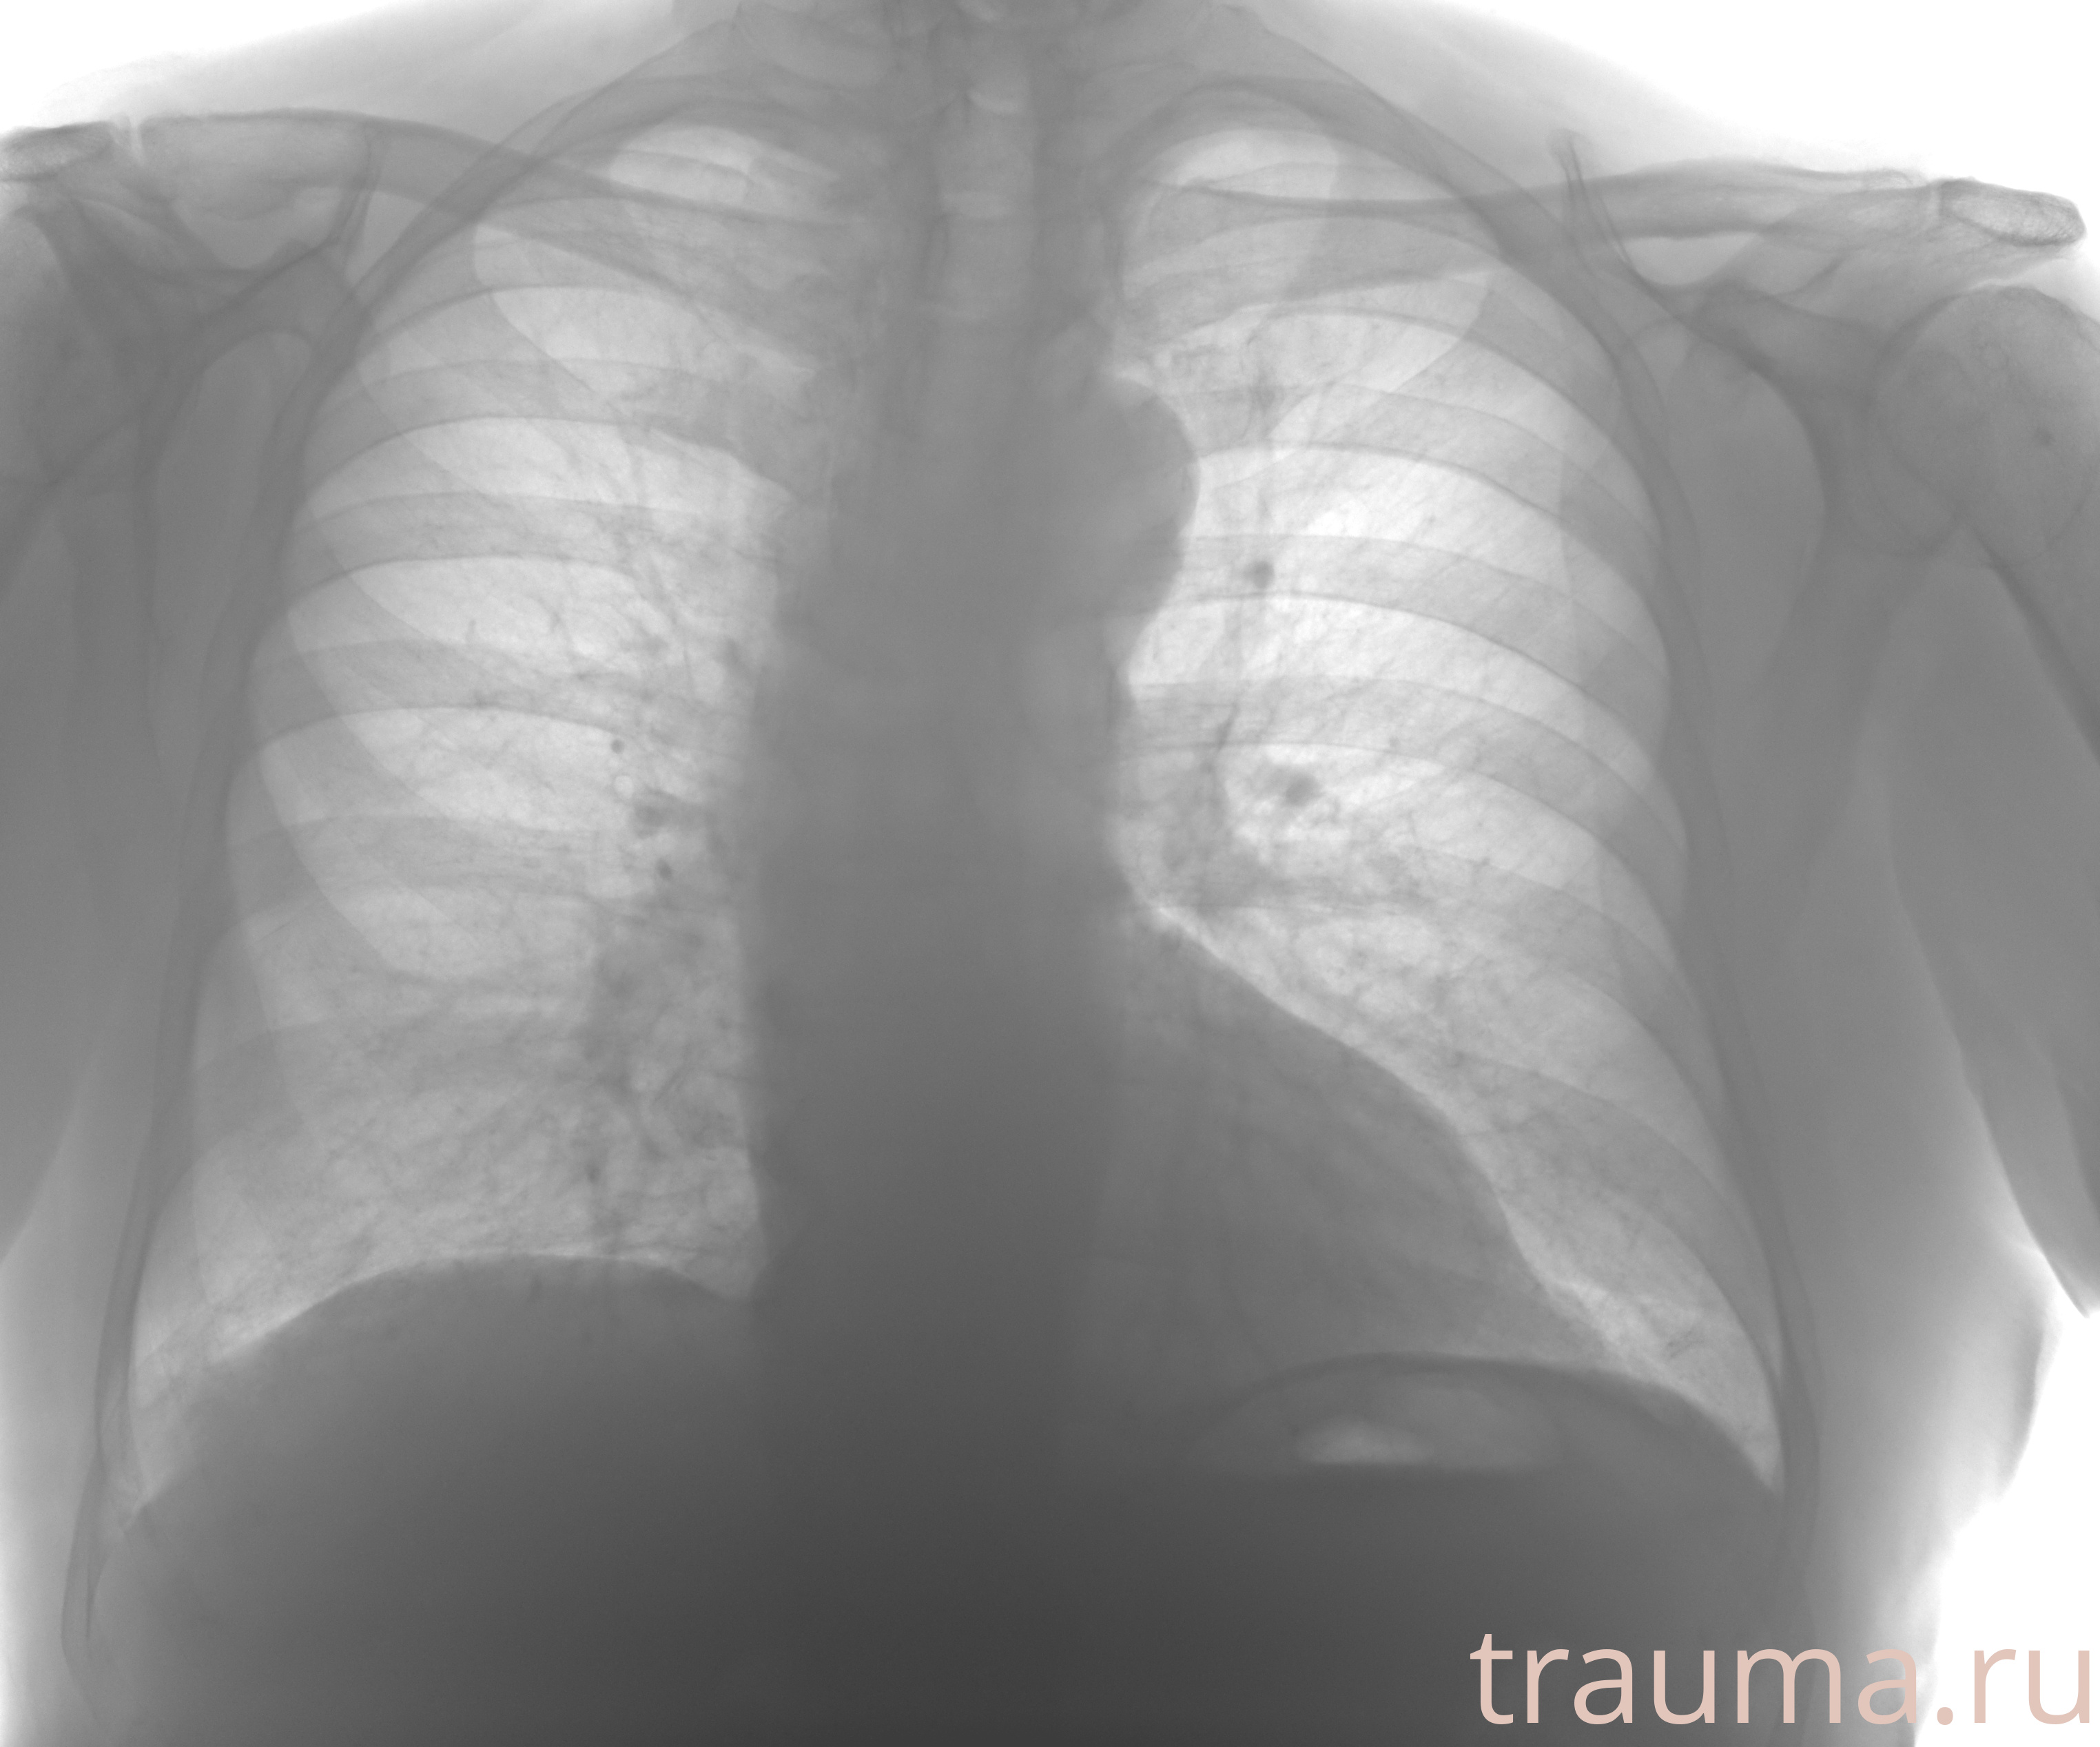

Рентген на дому: по вашему адресу приезжает врач-рентгенолог, травматолог-ортопед с мобильным рентгеновским аппаратом, проводит диагностику травмы или заболевания, делает необходимые рентгенограммы, дает рекомендации по дальнейшему лечению. Получить качественные снимки в домашних условиях возможно благодаря уникальной методике, разработанной МосРентген Центром для института  Склифосовского

Яркость: 1   Контраст: 1   Инвертировать: 0 Увеличение: 1

Перетаскивайте мышь вверх/вниз для контраста, влево/право для яркости. Прокрутка колесом изменяет масштаб. Нажмите Сбросить для возврата к исходному изображению. При увеличении держите мышь в той области, которую хотите рассмотреть.